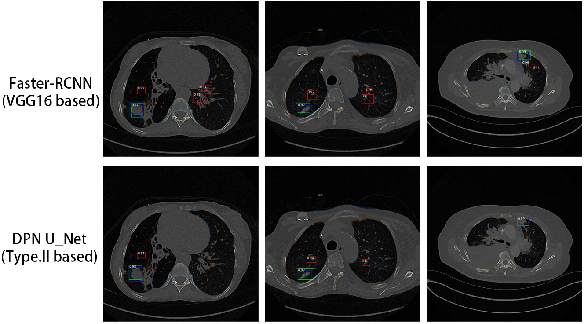

Abstract:Pulmonary cancer is one of the most commonly diagnosed and fatal cancers and is often diagnosed by incidental findings on computed tomography. Automated pulmonary nodule detection is an essential part of computer-aided diagnosis, which is still facing great challenges and difficulties to quickly and accurately locate the exact nodules' positions. This paper proposes a dual skip connection upsampling strategy based on Dual Path network in a U-Net structure generating multiscale feature maps, which aims to minimize the ratio of false positives and maximize the sensitivity for lesion detection of nodules. The results show that our new upsampling strategy improves the performance by having 85.3% sensitivity at 4 FROC per image compared to 84.2% for the regular upsampling strategy or 81.2% for VGG16-based Faster-R-CNN.